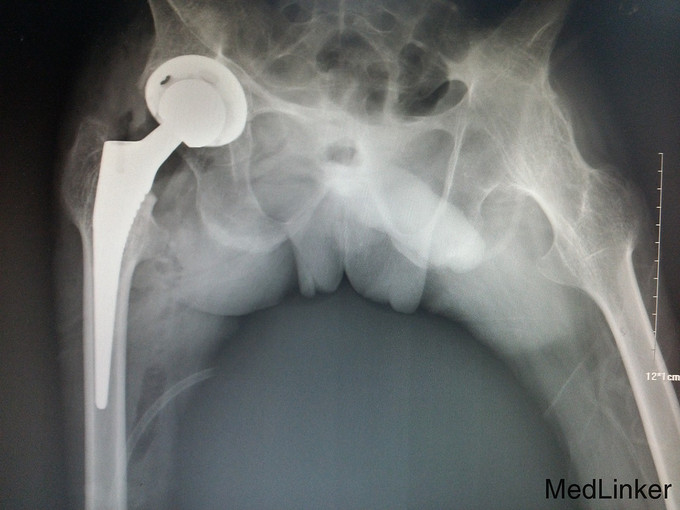

诊断:强直性脊柱炎(累及双侧髋关节) 患者腰骶部活动受限,影像学提示患者双侧骶髂关节间隙消失,且患者HLA—B27异常,强直性脊柱炎诊断明确。患者双髋关节间隙消失,活动度丧失,累及髋关节诊断明确。具有明确手术指症。患者既往关节鳞屑病,现控制稳定,经皮肤科会诊后排出手术禁忌症。由于经济稳定,患者及家属决定分次手术,本次手术暂行右侧人工全髋关节置换术。

讨论: 经验:强直性脊柱炎累及双髋的患者行全髋关节置换术时,显露及找到髋臼是手术的重点和难点。 1.显露。由于髋关节强直,失去活动度,助手在不能旋转大腿,造成显露困难。我们的做法是先充分显露小粗隆,沿小粗隆上方约2cm处截骨(一般常规于小粗隆上方0.5-1cm处截骨),充分离断头颈部,此时助手可通过内旋患肢,充分显露。下一步再按常规行小粗隆上截骨。 2.清除瘢痕组织。此类患者由于长期髋部强直,活动受限,周围往往会形成瘢痕挛缩,多以内收肌紧张常见。故显露的过程需彻底清除周围瘢痕组织。术中安装假体后测试关节各方西活动,若内收肌紧张,需行内收肌松解。 3.找髋臼。由于强直性脊柱炎累及髋关节需行关节置换的患者,往往头与髋臼已经发生融合,术中很难判断髋臼。若贸然凿除所谓的股骨头,很可能会破坏髋臼壁。故找髋臼时性循序渐进,逐渐凿骨找到髋臼。CT片显示头与髋臼底之间仍有间隙存在,故可推断圆韧带仍存在,这也是这类患者的特点。故逐渐凿除股骨头时,到达圆韧带的层面时就找到了髋臼底。此时可开始磨钻磨锉髋臼。从小号开始依次增大号数。 4.骨质。强直性脊柱炎的患者因长期服用激素类药物,骨量丢失较正常人较多,故髋臼骨质疏松明显,所以磨搓髋臼时需反转,防止骨量过度丢失,磨穿髋臼。 不足:1.术中由于患者左髋强直,摆放手术体位受限,不能维持身体中立位,身体后仰,术中安放臼杯时未能把握合适的前倾角度。 2.假体的选择。由于术前未认真评估股骨髓腔的形态,导致术中按常规选择股骨假体柄后,出现假体柄打入困难。该患者股骨髓腔形态呈烟囱型,最好选择直柄,打入后可更贴合,方便骨长入。